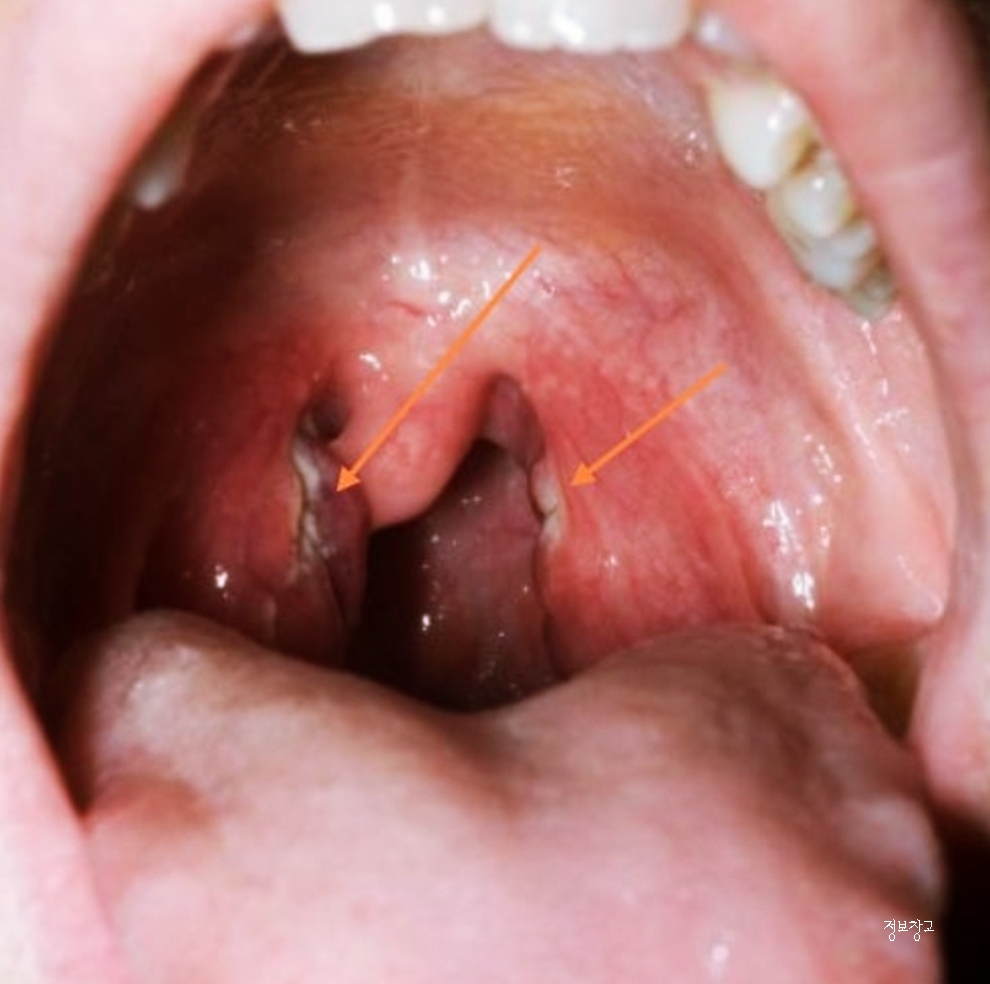

④ 세균성 인후염 또는 편도염

고열, 심한 통증, 삼킬 때 통증이 강하다면

단순 바이러스가 아닌 세균성 인후염 가능성도 있습니다.

이 경우에는 자연 회복이 어렵고

적절한 치료가 늦어지면 증상이 오래 지속되거나 재발할 수 있습니다.

- 고열 또는 편도에 하얀 분비물